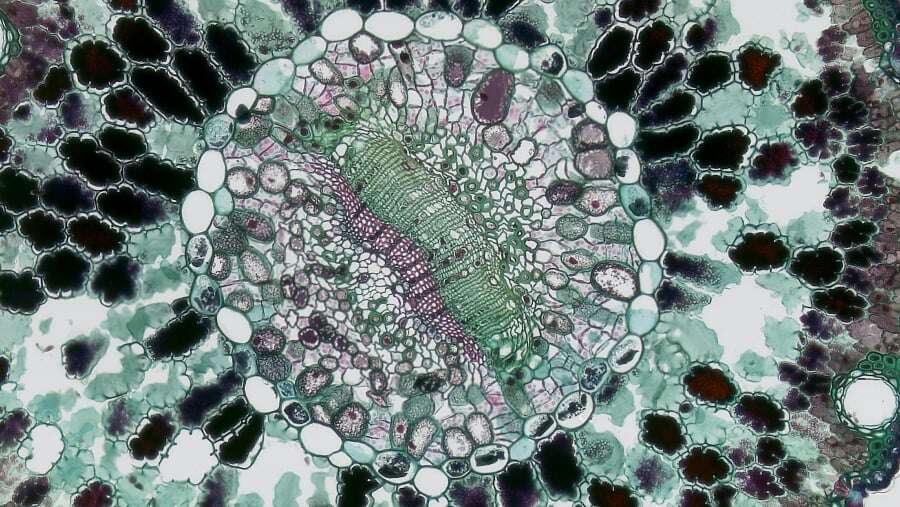

Ψηφιακή ακτινογραφία (χαρακτηριστική εικόνα σαν φύλλα κρεμμυδιού από την αντίδραση του περιοστέου και λυτική βλάβη στο οστό).

Βιοψία με βελόνη για την επιβεβαίωση της διάγνωσης και την έναρξη της θεραπείας. Χωρίς αποτέλεσμα βιοψίας δεν πρέπει να ξεκινάει η θεραπεία. Συνιστάται η βιοψία με βελόνη καθοδηγούμενη από αξονικό τομογράφο και να αποφεύγονται οι ανοικτές βιοψίες.